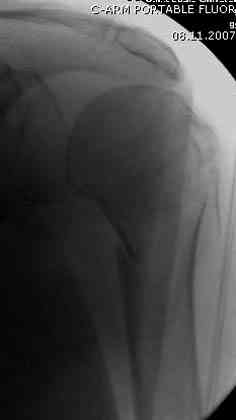

Наш недавний случай перкутанной фиксации "методом

Сиэтла" спицами 2.8 мм с резьбой на конце.

Под проводниковой анестезией произвел попытку закрытой репозиции на 10-е сутки, вроде бы неплохо получилось.

Наличие рентген контроля (ЭОП) помогает во время

репозиции и фиксации, но многие коллеги умудряются без рентгена фиксировать несколькими спицами перкутанно.